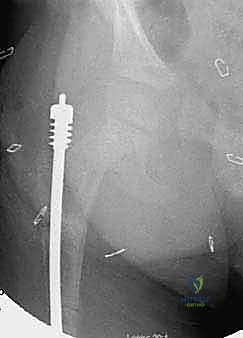

الدليل التفصيلي لخطوات العملية الجراحية: بضع العظم عبر الجلد والمسامير التلسكوبية

تُعد هذه العملية من أدق العمليات في جراحة عظام الأطفال، وتتطلب مهارة استثنائية كما هو الحال مع البروفيسور محمد هطيف. يتكون المسمار التلسكوبي (Fassier-Duval) من جزأين يتداخلان ببعضهما البعض (مثل التلسكوب). يتم تثبيت أحد الأطراف في أعلى العظم والطرف الآخر في أسفله. عندما ينمو العظم، ينزلق الجزء الداخلي من المسمار للخارج، مما يسمح للعظم بالنمو الطبيعي دون أن ينثني أو ينكسر.

الخطوة الرابعة: إدخال المسمار التلسكوبي

بعد تقويم العظم وجعله مستقيماً كحبات المسبحة على خيط، يتم إدخال السلك الدليلي (Guide Wire). ثم يتم إدخال الجزء الخارجي (الأنثوي) من المسمار التلسكوبي وتثبيته في الجزء العلوي من العظم (Epiphysis).

بعد ذلك، يتم إدخال الجزء الداخلي (الذكري) من المسمار عبر الجزء السفلي من العظم وتثبيته في المشاشة السفلية. هذا التصميم العبقري يضمن حماية العظم بالكامل من الداخل.